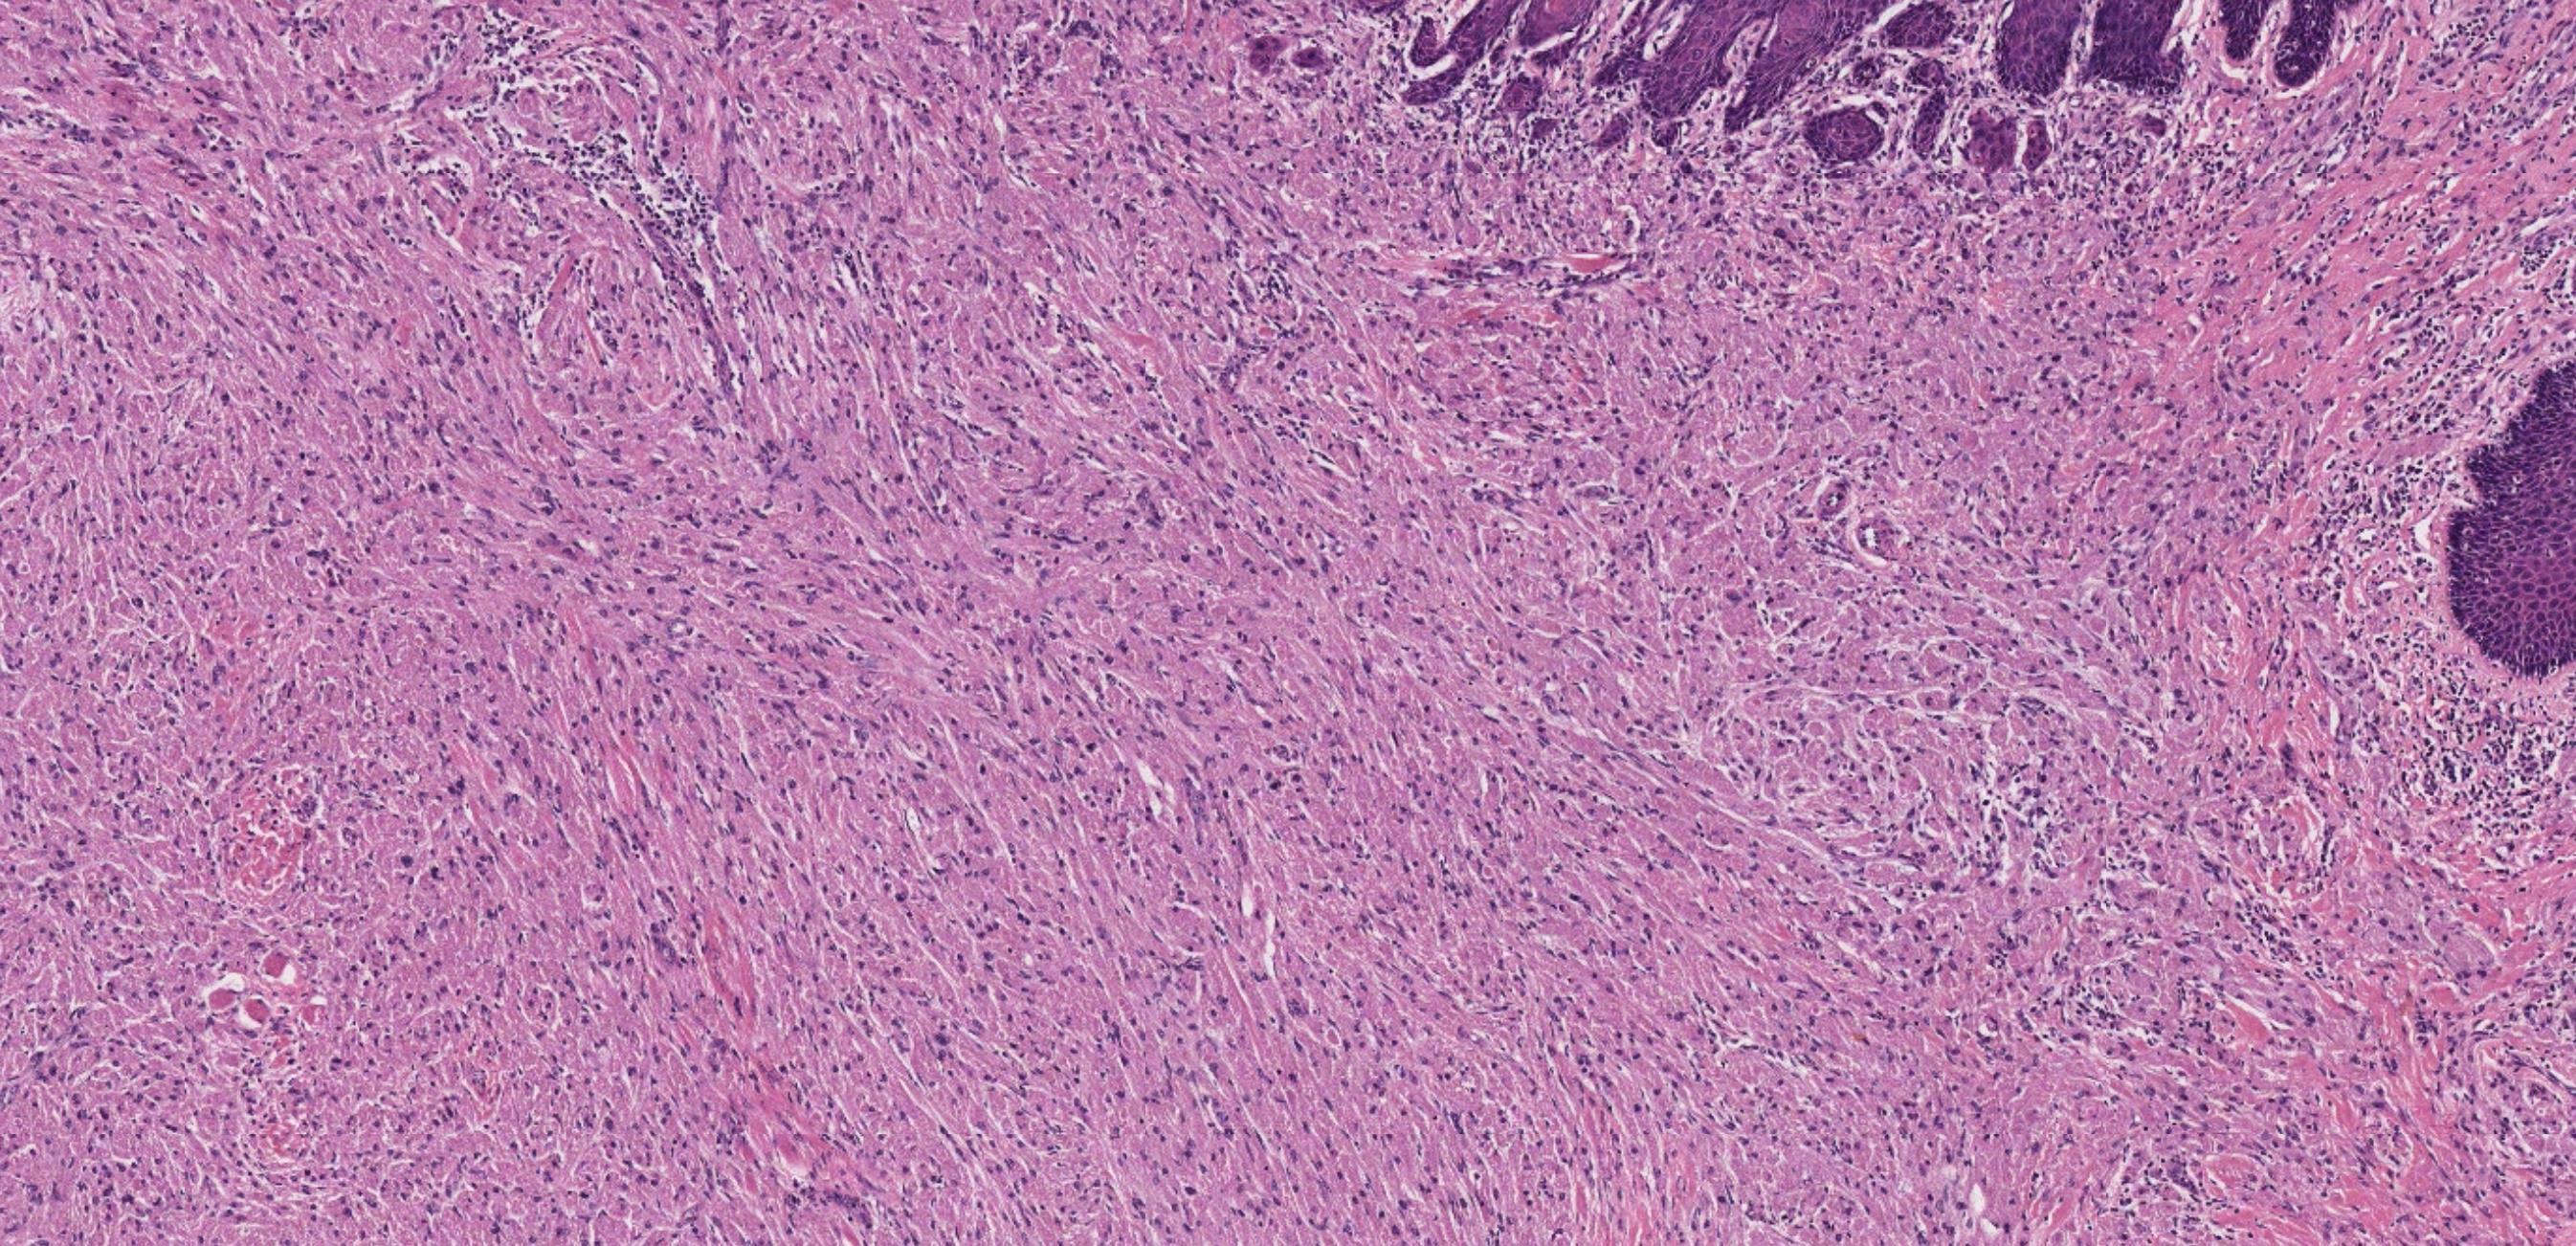

• Nodular mucosa with circumscribed tumour with infiltrative periphery • Large cells with eosinophilic granular cytoplasm • Is surface epithelium normal?

Case 4- Salient points

??

Case 4 Diagnosis

Granular cell tumour